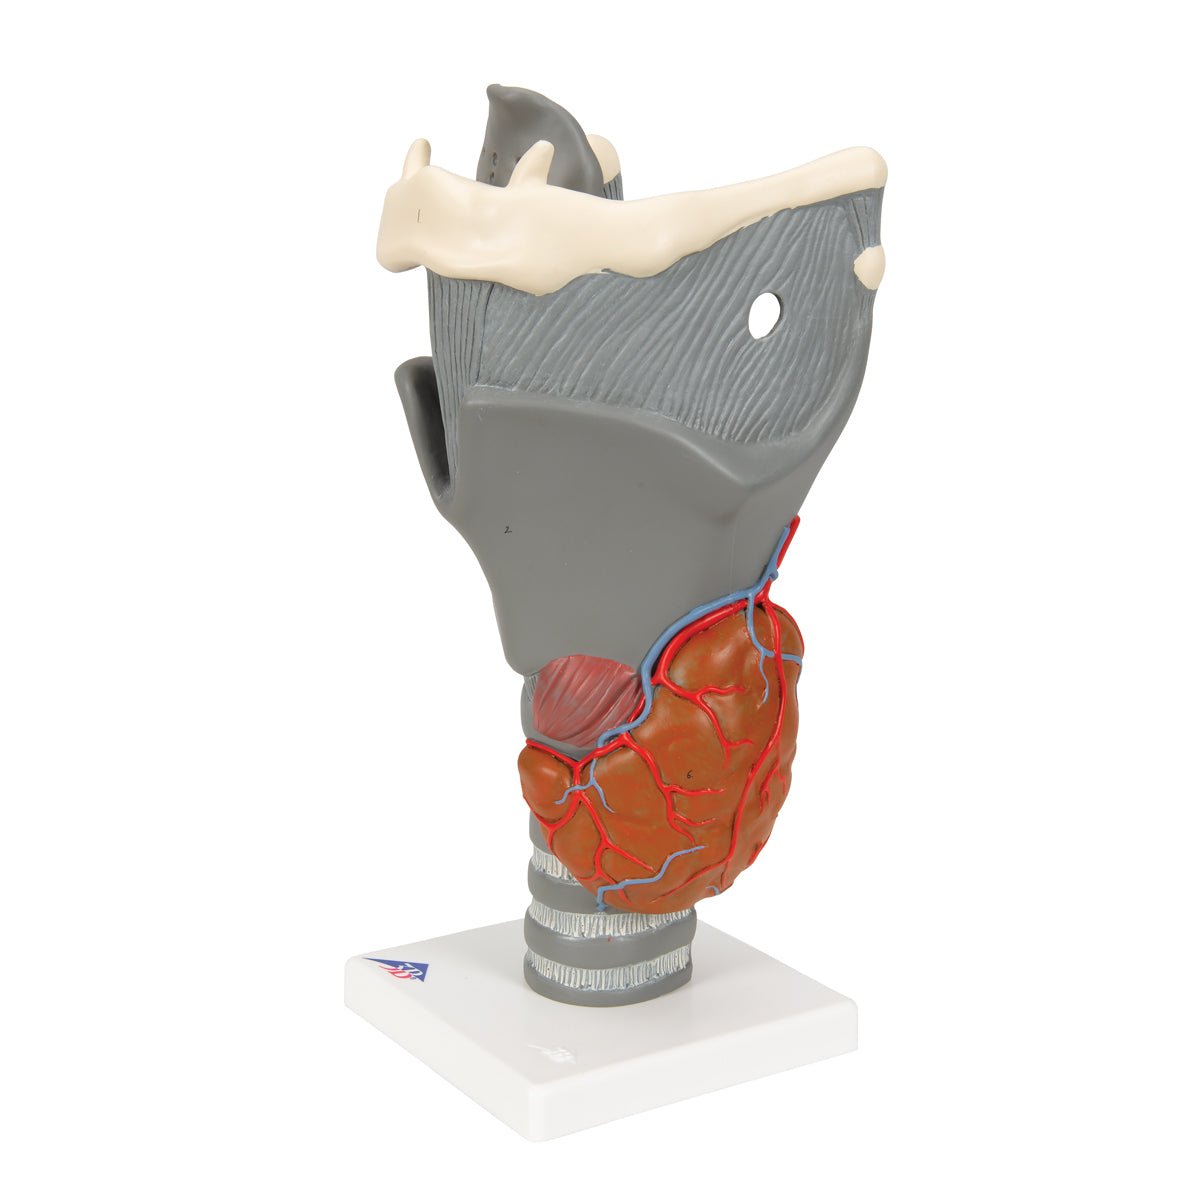

Salg af anatomiske modeller er det bærende element i eAnatomi, selvom vi også bruger mange ressourcer på at udvikle vores egne anatomiske materialer som fx plakater. Anatomiske modeller anvendes til forskellige formål og kan både vise afgrænset væv, organer samt organsystemer. Søger du en simpel model af knoglevæv eller måske en avanceret torso-model baseret på MRI teknologi, kan du finde det hele på eanatomi.com.